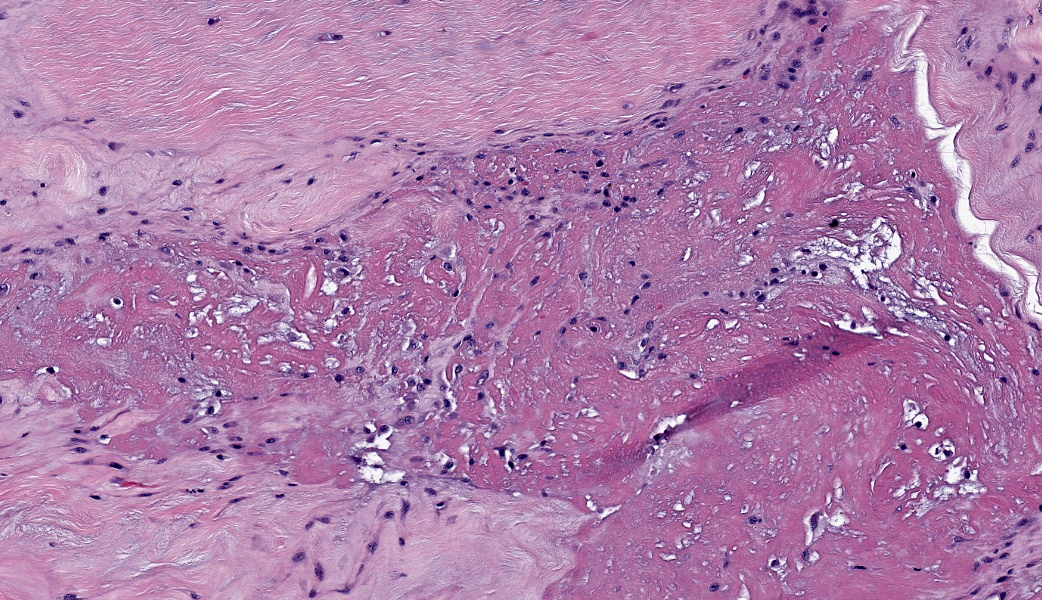

Suspensory ligament, right rear branch. Compared to a branch of the clinically normal right front suspensory ligament, collagen fibers are irregular and often form intersecting or divergent bundles. In many areas, there are fewer fibroblasts among collagen fibers than in the normal control. Throughout the tissue, wavy tendrils of pale basophilic, Alcian blue-positive matrix dissect between collagen bundles. Similar material surrounds increased numbers of variably sized, dilated and tortuous blood vessels. These vessels have thin walls and are lined by plump endothelial cells, and are often surrounded by loosely arranged stellate cells. In other areas, there is chondroid metaplasia, with clustered and individual chondrocyte-like cells in lacunae surrounded by amorphous, pale basophilic matrix, which is sometimes faintly mineralized. There is rare hemorrhage.Contributor's Morphologic Diagnoses:

The terms degenerative suspensory ligament desmitis (DSLD) and suspensory ligament degeneration (SLD) are used somewhat synonymously, with DSLD often used to describe horses with a clinical diagnosis of suspensory ligament degeneration, and SLD used to describe histologic findings in the suspensory ligaments of horses that may or may not have a clinical diagnosis of DSLD. DSLD causes chronic, progressive multi-limb lameness of variable severity, often recognized by enlarged, hyperextended or dropped fetlocks.8 The rear limbs are typically more affected.3,8 In addition, the terms suspensory ligament desmitis or suspensory ligament desmopathy may be used to describe any of a variety of clinically or ultrasonographically detected injuries anywhere along the length of the suspensory ligament.3 Histology is rarely performed in these cases, especially in the acute phase, and it is unclear if these injuries are related to degenerative changes.3Histologic changes in SLD/DSLD include loss of longitudinal arrangement of collagen fibers, proteoglycan accumulation, presence of chondrocytes, hemorrhage, vascular proliferation, and widened interstitial connective tissue septa.4,6 Despite the use of the term desmitis, inflammatory cells are not present.4 These changes are reported to be more severe in the branches of the suspensory ligament than in the body or origin of the ligament.3,5

The major histologic findings within ligaments suffering from SLD include loss of longitudinal arrangement of collagen fibers (disorganization), proteoglycan accumulation (increased ground substance), presence of chondrocytes (chondroid metaplasia), hemorrhage, vascular proliferation, widened interstitial connective tissue septae, and a lack of inflammatory cells.8 As this disease develops, regardless of cause, degenerating collagen fascicles blend together and there is either death of the tenocytes/ligamentocytes or metaplasia of tenocytes/ligamentocytes into chondrocytes. Fibrosis develops within and around the ligament and is usually associated with hypertrophied tenocytes/ligamentocytes. These areas are generally interpreted as failed attempts at repair.